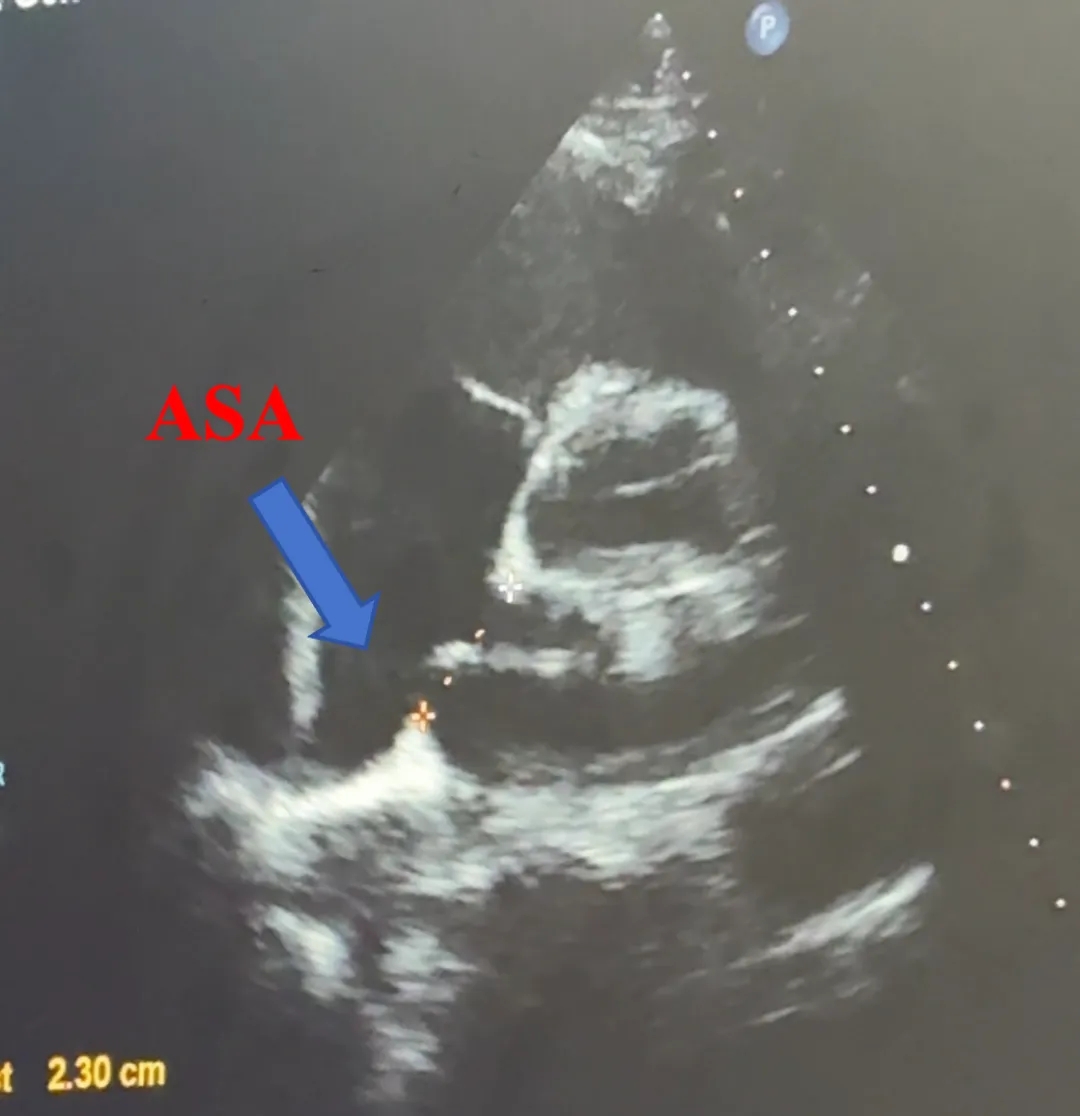

主动脉短轴切面

合并房间隔膨出瘤

缺损+房间隔膨出瘤23.0mm